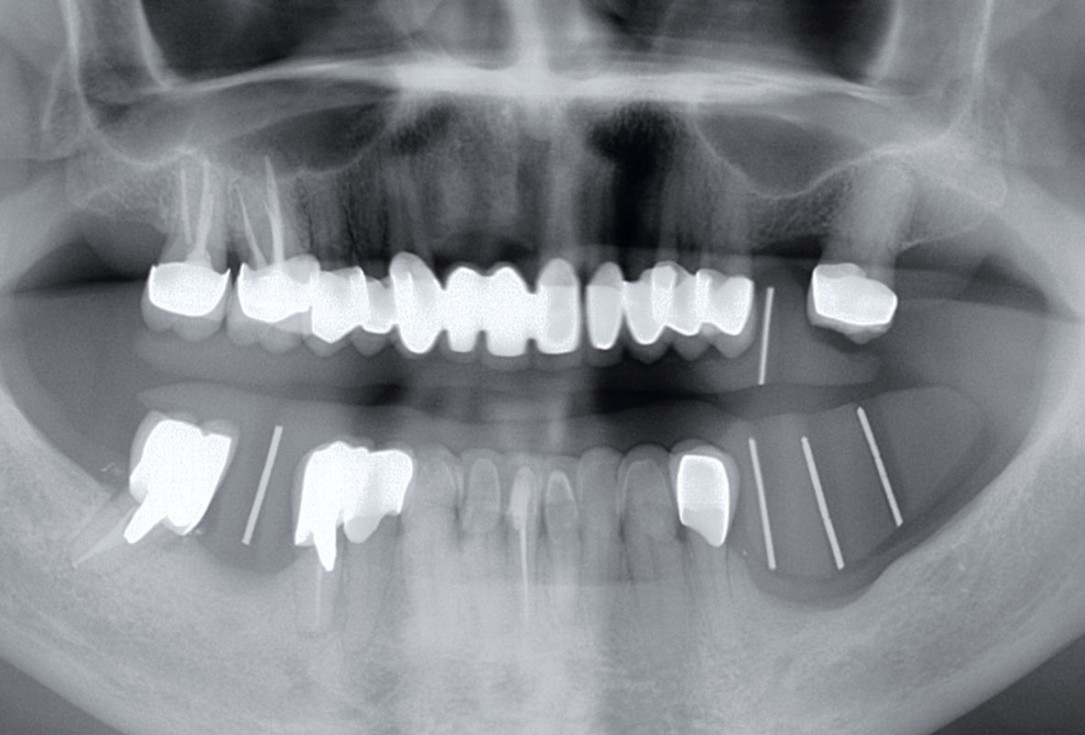

02/12 - Mandibular bone defect in area 35-37

Ridge augmentation in the mandible with maxgraft® bonebuilder in a free-end situation - Dr. Dr. Dr. O. Blume